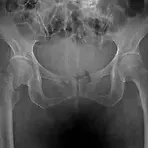

뼈에도 악성종양이 생긴다. 대한민국 질병 사망률1위의 원인은 단연 암이다. 이것은 인류에게 이미 상식적으로 통용되고 있으며 의학이 발달함에 따라 암을 어느정도 완치하게 되었지만 사실상 아직까지도 암이라고 하면 인류에게는 절망적인것이다. 우리가 생각하는 암은 악성종양세포로 세포가 손상되어 산성화 작용에따라 세포가 기형적으로 변하여 악성종양세포로 변이하여 증식하는 것이 대부분이며, 암은 통상 폐, 위, 간, 대장, 십이지장, 식도, 뇌와 같은 우리몸속의 내과적 장기에 많이 나타난다고 알고있다. 하지만 이러한 악성종양이 뼈에도 나타나는것과 뼈에도 암이 생긴다는 사실을 알고있는가? 배우 유아인의 군면제 사유로 한창 화제가 되고 이슈가 되었던, 배우 유아인이 밝힌 골육종, 뼈에 암이 생기는 질병의 병명이다. 오늘..